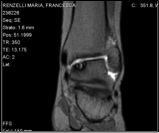

Una radiografia standard della caviglia associata ad una RM sono spesso sufficienti allo specialista ortopedico per determinare la causa del difetto cartilagineo ed impostare un corretto approccio terapeutico.